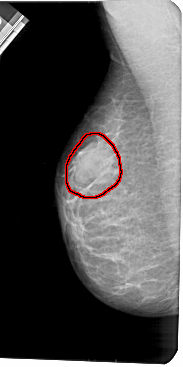

A_1419_1.LEFT_MLO

LEFT_MLO LINES 5491 PIXELS_PER_LINE 2731 BITS_PER_PIXEL 12 RESOLUTION 43.5 OVERLAY

FILE: A_1419_1.LEFT_MLO.OVERLAY

TOTAL_ABNORMALITIES 1

ABNORMALITY 1

LESION_TYPE MASS SHAPE OVAL MARGINS OBSCURED

ASSESSMENT 4

SUBTLETY 4

PATHOLOGY BENIGN

TOTAL_OUTLINES 1

BOUNDARY